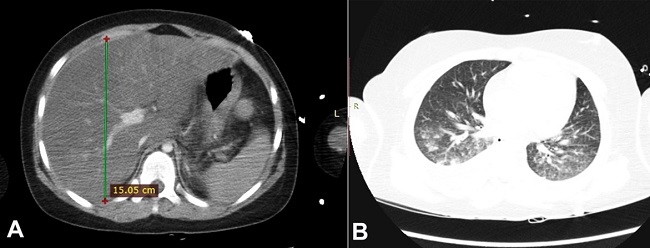

Metabolic compensation and monitoring of the vital functions were promptly started. On admission, serum aminotransferases levels were: AST 10U/l (RR: 38U/I), ALT 9 U/l (RR:30U/I). During the first two days of hospitalization, serum glucose levels were lowered to 260mg/dl (RR: 70-99mg/dl), metabolic acidosis and sodium levels were equalized. Potassium levels remained slightly below the lower limit of normal. On the following day, consciousness deterioration and respiratory distress ensued. The patient was intubated and placed on mechanical ventilatory support. A brain CT scan was normal, and the blood cultures were negative. Due to the increase in inflammatory parameters, empiric broad-spectrum antibiotic therapy was initiated. On the fourth day (D4) of hospitalization, an increase of the abdominal girth and the elevation of aminotransferases were detected (ALT 3559 U/l (RR: 30U/I), AST 9026 U/l (RR: 38U/I)) (Table 1). A thoracic and abdominal contrast-enhanced CT scan was performed, which showed hepatomegaly (longitudinal dimension of the right lobe - 150.5mm (RR: 105mm), diffuse steatosis (liver attenuation was approximately 30 Hounsfield Units (HU) less than the spleen (RR: <10HU) (Figure 1A), and bilateral pulmonary parenchymal consolidations consistent with bronchopneumonia (Figure 1B). Liver vessels were patent. It also showed a blurred outline of the pancreas with a small amount of peripancreatic fluid, without typical features of acute pancreatitis.